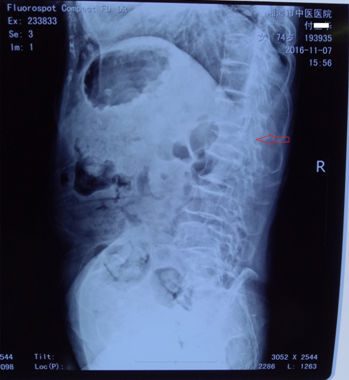

入院時(shí)X線片,腰1椎體壓縮骨折